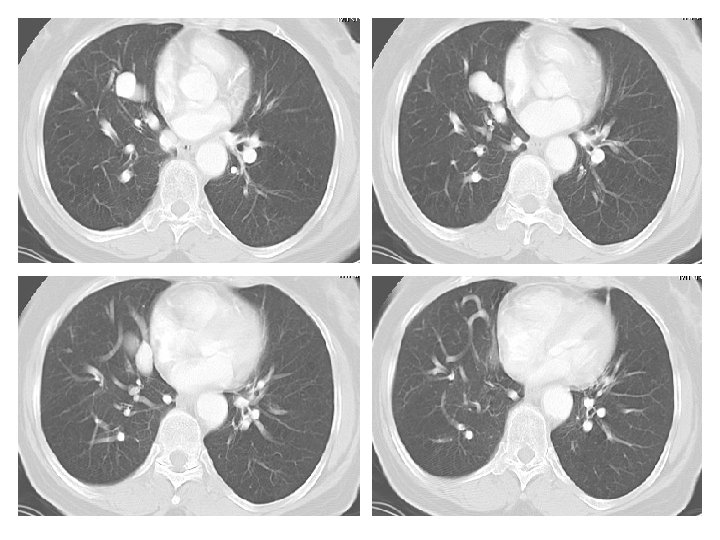

Case History 65 year old male with shortness of breath. Images: PA and Lateral View of the chest. CT of the Chest with IV contrast presented in lung windows. Please note that the images proceed from left to right and top to bottom.

Findings and Differentials Findings: The frontal view of the chest shows multiple prominent tubular structures arising from the right hilum and coursing inferiorly adjacent to the right heart border. There are multiple dilated tubular structures seen in the right lung on CT. Tubular structures within the lung are either vascular or bronchial. If bronchial, they would have to be filled with inspissated mucus to be opaque. But there are bronchi seen adjacent to these tubular structures and the bronchi are normal. The tubular structures therefore represent dilated pulmonary arteries and veins. The remainder of the right lung is normal. There also several calcified lymph nodes from prior granulomatous disease. The cardiac silhouette is normal. There are no pleural effusions. Differential: • Total Anomalous Pumonary Venous Return • Pulmonary AVM • Scimitar Syndrome

Discussion These findings are diagnostic of pulmonary AVMs are believed to be congenital defects in the terminal capillary loops that result in dilatation and formation of vascular sacs. 40 -65 percent of patients with pulmonary AVMs also have AVMs elsewhere (skin, CNS, solid organs). AVMs are seen in Osler-Weber-Rendu disease. Pumonary AVMs appear on imaging as vascular masses adjacent to the pleura or the bronchovascular bundles. They are common in the lower lobes. The draining veins are usually larger in size compared to the feeding arteries. They usually do not cause symptoms but can cause hemoptysis. Due to the right to left shunting, pulmonary AVMs are associated with cerebral abscesses. The right to left shunting also decreases the Pa. O 2 and causes the cardiac output to increase. Angiography is seldom needed to diagnose the condition. The CT findings of multiple dilated pulmonary vessels clinches the diagnosis. It is important to show the feeding artery and draining vein. Catheter embolization is the preferred treatment modality. Dilated bronchi filled with inspissated mucus can mimic this condition.